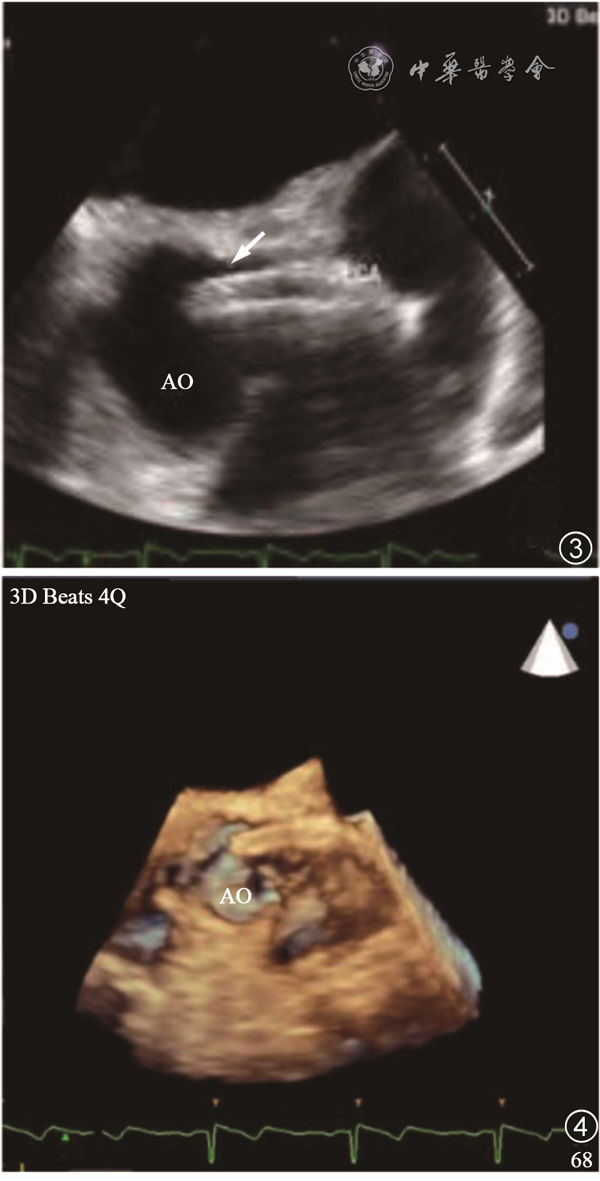

患者,女性,58岁,当地医院超声心动图检查发现主动脉异常占位,为进一步明确诊断于2020年6月来四川大学华西医院就诊。患者2019年2月因冠状动脉粥样硬化性心脏病,左冠状动脉前降支开口狭窄95%,中段狭窄60%于当地医院接受了经皮冠状动脉支架植入(percutaneous coronary intervention,PCI)术。术后偶有胸闷,余无明显不适。2019年6月生化检查:脑钠肽前体(Pro-BNP)274.10 pg/ml(正常参考值范围0.00~300.00 pg/ml),心电图提示窦性心动过缓(心率50次/分)。2020年6月就诊华西医院行常规经胸超声心动图(transthoracic echocardiography,TTE)检查,胸骨旁长轴切面可见主动脉根部一强回声占位(图1),胸骨旁短轴切面(图2)和经食管超声心动图(transesophageal echocardiography,TEE)短轴切面(图3)及三维TEE短轴切面(图4)均可见左冠状动脉主干管腔内总长度约30 mm、内径约2.6 mm的双线状支架样结构,一端位于左冠状动脉前降支开口处,另一端伸入主动脉根部管腔内约17 mm,彩色多普勒血流成像(colour Doppler flow imaging,CDFI)显示支架内血流通畅。左冠状动脉前降支近段内径约1.4 mm,右冠状动脉主干近段内径约2.0 mm。主动脉瓣开闭活动未受影响。二维斑点追踪超声心动图左心室整体纵向应变(global longitudinal systolic,GLS)牛眼图分析显示左心室收缩功能正常,无节段性室壁运动异常(图5)。

图3 经食管超声心动图短轴切面显示左冠状动脉内支架突入主动脉根部管腔内(箭头所示)图4 三维经食管超声心动图显示左冠状动脉内支架突入主动脉根部管腔内

注:AO为主动脉